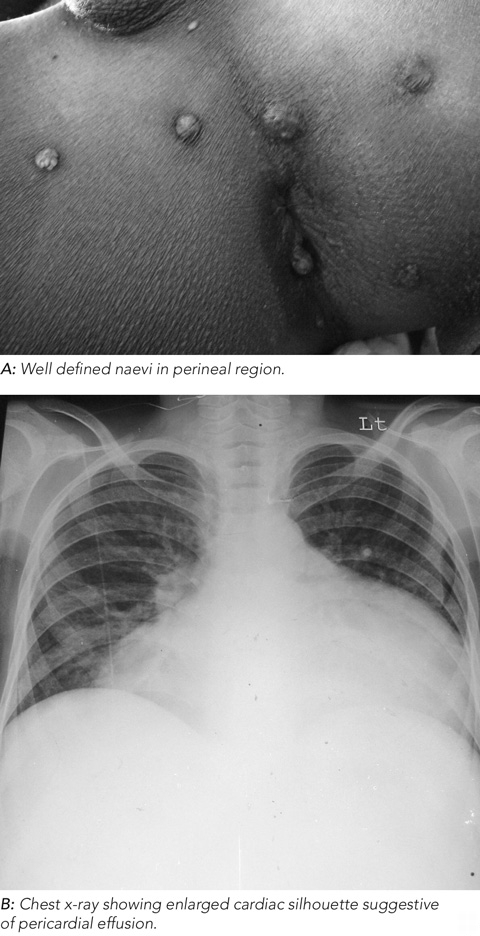

On examination, the patient had multiple, blue-black, papular and nodular, compressible, non-pulsatile, vascular skin lesions, ranging in size from a few millimetres to 1–2 cm, distributed over the trunk and limbs, including the soles of the feet, perineal region (Figure A) and lips. A chest x-ray showed an enlarged cardiac silhouette suggestive of pericardial effusion (Figure B). This was confirmed by transthoracic echocardiography. Therapeutic pericardiocentesis showed haemopericardium.

Blue rubber bleb naevus syndrome (Bean syndrome) is diagnosed in the presence of distinctive venous malformations on the skin, in the gastrointestinal tract and, less often, in other organs, leading to occult or overt gastrointestinal bleeding and chronic anaemia.1-3